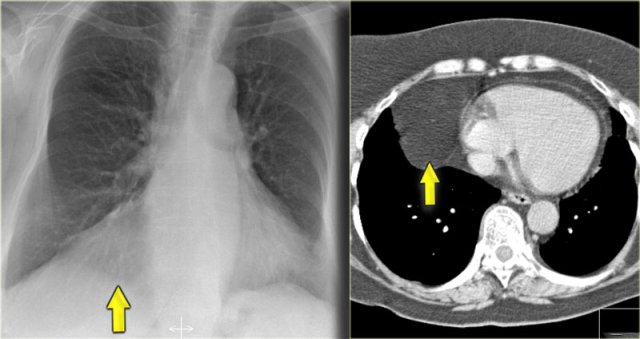

Hidden areas (3)

Here a pneumonia which was hidden in the right lower lobe mainly below the level of the dome of the diaphragm (yellow arrow).

Notice the increase in density on the lateral film in the lower vertebral region.

You may have to enlarge the image to get a better view.